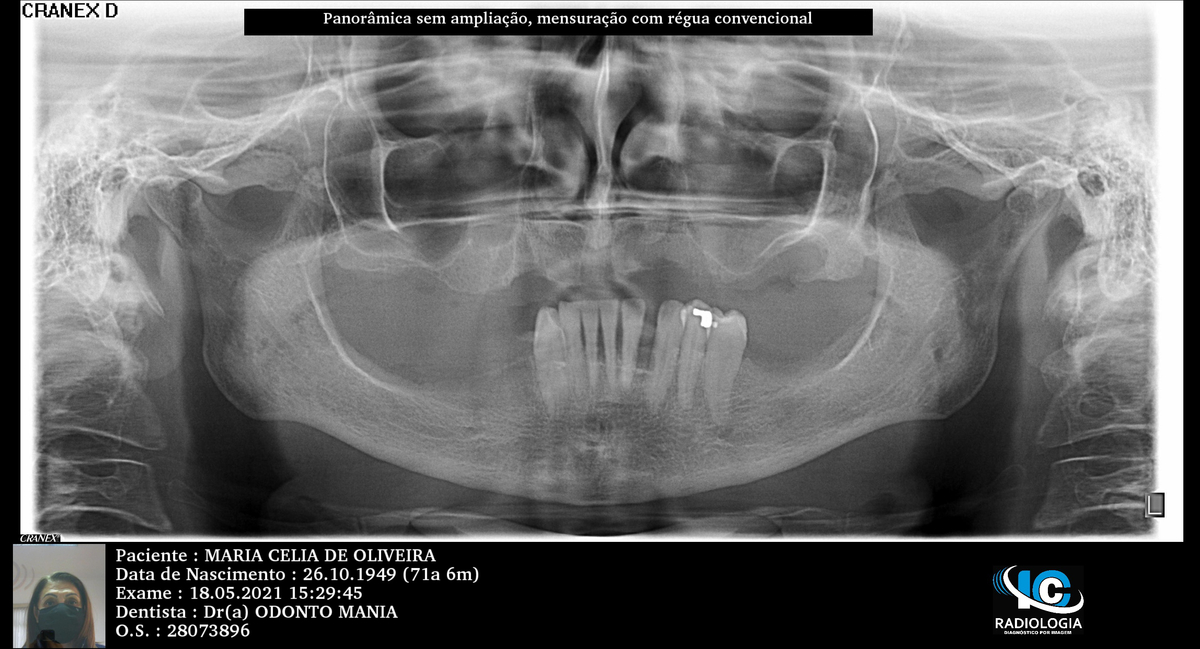

PRÓTESE TOTAL FIXA EM IMPLANTES

M.C.O.